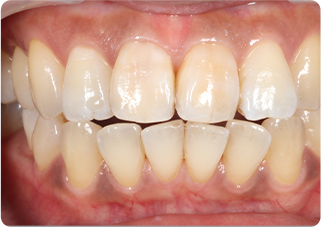

セラミッククラウン症例②

術前

仮歯

術後

| 主訴 | 前歯を綺麗にしたい、隙間が気になる |

|---|---|

| 治療期間/回数 | 4ヵ月、6回 |

| 価格(税込) | 792,000円(税込) |

| リスク・副作用 | セラミック破損の可能性 |

| ポイント | 仮歯で歯ぐきの状態を整え、自然な色、形となるようにオーダーメイドでセラミックを盛り、クラウンを作製した。 |